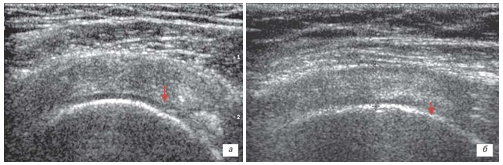

Высокую эффективность терапии препаратами коллагена для внутрисуставного и периартикулярного введения и геля на основе полинуклеотидов подтверждено результатом УЗИ исследованием и МРТ (рис.3, 4,5).

/Scherbakov.files/2.png)

А ˗ до лечения В – после лечения

А – до лечения: у пациента с адгезивным капсулитом определяется утолщение капсулы и уменьшение объема подмышечного заворота.

Основные проявления: боль и прогрессирующее снижение объема движений в плечевом суставе. В ˗ после лечения: у пациента восстановление капсулы и увеличение объема подмышечного заворота.

Отсутствие болевого синдрома и увеличение объема движений в плечевом суставе.

Рисунок 5. МРТ картина адгезивного капсулита до и после лечения